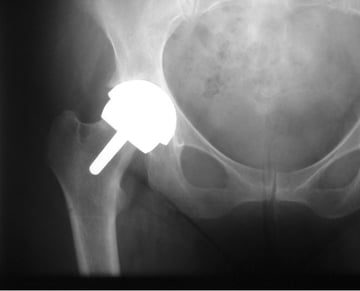

The hip seen above after a Birmingham Hip Resurfacing

The hip resurfacing which I routinely use is a Birmingham hip resurfacing.  This type of resurfacing was originally developed by my colleague Mr Derek McMinn working at the Royal Orthopaedic Hospital.  At the time Mr McMinn was the first individual in the world to undertake metal on metal hip resurfacing and I was able to start using the device very soon after it was introduced.  The present device was introduced in 1997 after further development work with my colleague, Mr Ronan Treacy.